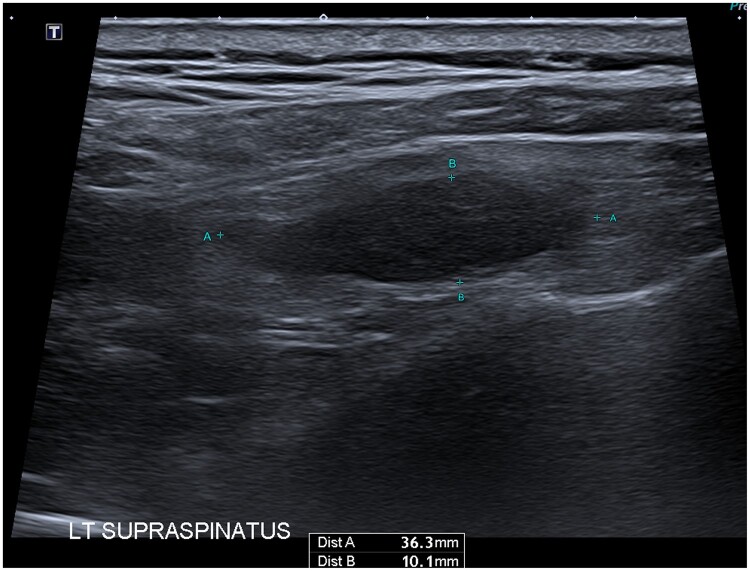

颗粒细胞瘤是一种罕见的、多为良性的软组织神经外胚层肿瘤,最常见于皮肤和周围软组织。迄今为止,还没有关于颗粒细胞瘤 PSMA-PET 阳性的出版物。在这名 60 岁的男性身上,对局部中危前列腺癌进行 PSMA-PET 分期治疗时意外发现了一个 PSMA 亲和性左上肌病变,随后经活检证实为颗粒细胞瘤。我们介绍了首例PSMA-avid颗粒细胞瘤病例,并补充了越来越多关于PSMA-PET在前列腺癌以外的良性和恶性病变中的avidity的文献。

Granular cell tumour is a rare, mostly benign, soft tissue, neuroectodermal tumour, most commonly seen in the skin and peripheral soft tissue. There are no publications to date of PSMA-PET avidity in a granular cell tumour. In this 60 year old male, staging PSMA-PET for a localized intermediate risk prostate cancer incidentally identified a PSMA-avid left supraspinatus lesion, which was subsequently biopsy-proven as a granular cell tumour. We present the first case of PSMA-avid granular cell tumour and add to the growing literature documenting PSMA-PET avidity in benign and malignant lesions apart from prostate cancer.